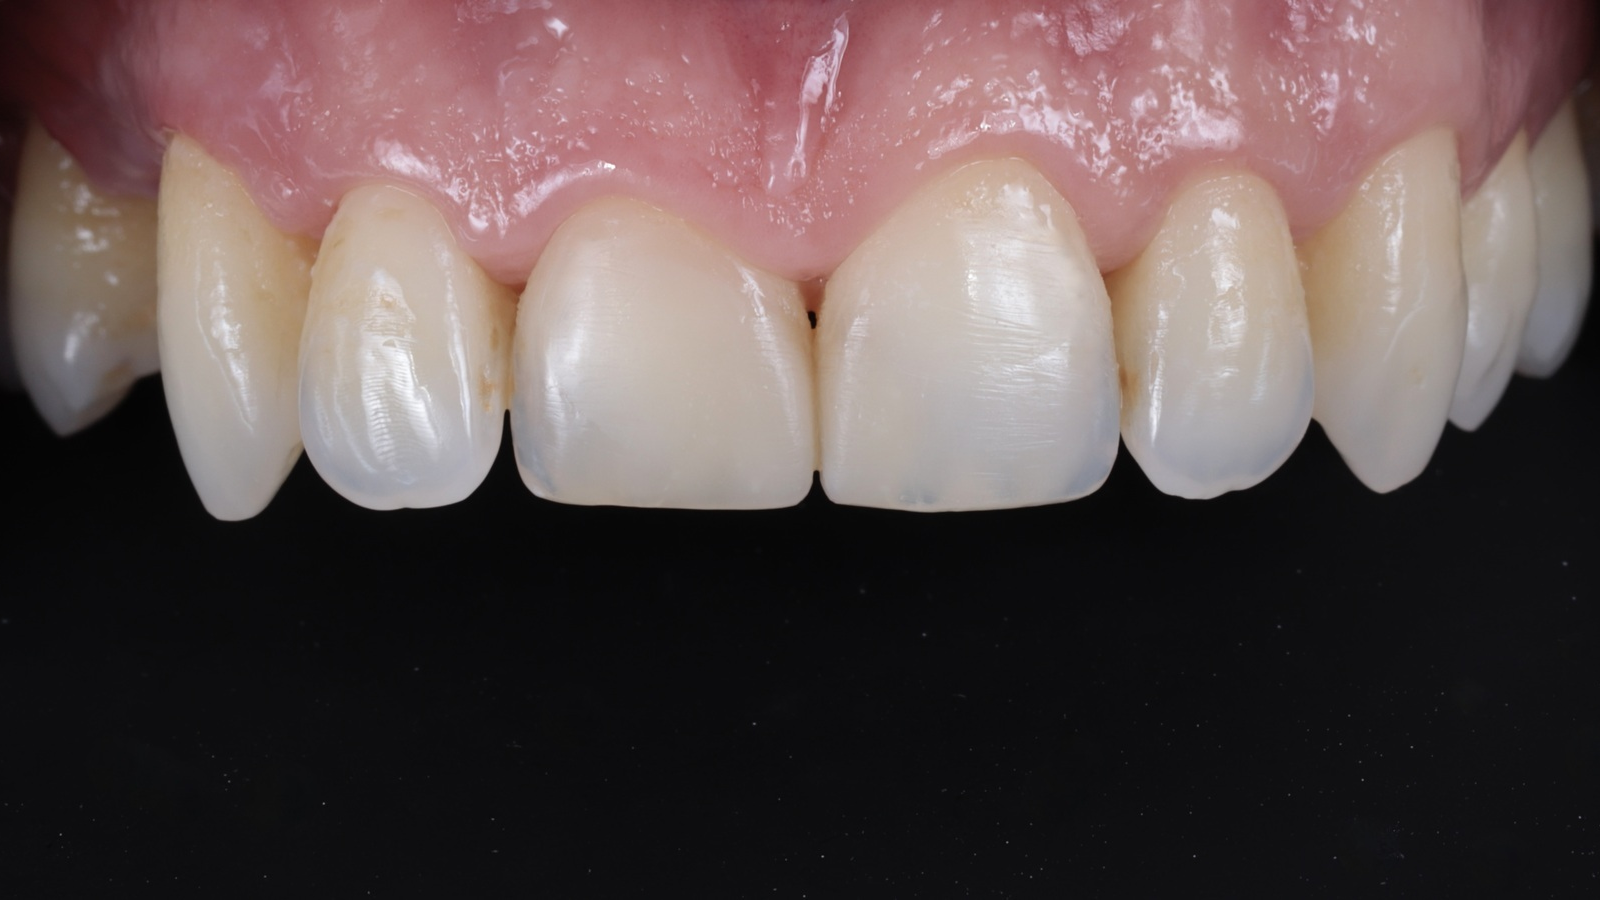

The dam was removed, and the finally polished restorations were revealed.

The restorations achieved complete integration with the natural tooth tissue after rehydration. The composite independently developed areas of translucency based on the thickness created, resulting in a highly aesthetic and natural appearance.